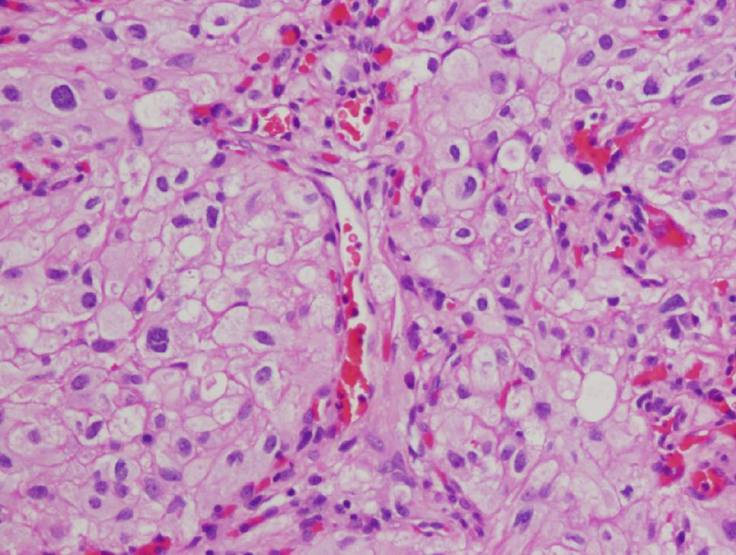

Hemangioblastoma is highly vascular tumor with neoplastic stromal/interstitial cells that have a variably clear cell appearance due to their lipid and glycogen cytoplasmic contents. Hemangioblastomas can be found in patients with von Hippel Lindau (VHL) syndrome, who also have increased risk of developing renal cell carcinoma (RCC). Immunostains can be used to differentiate the inhibin-positive hemangioblastoma from metastatic clear cell RCC, which is positive for PAX2/PAX8, CD10, and RCC.